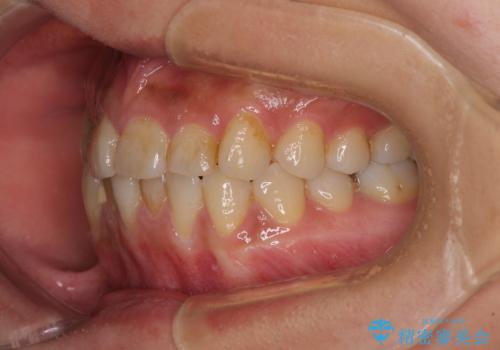

前歯のデコボコとクロスバイト インビザラインによる矯正治療

- 上下のクロスバイトと前歯のデコボコを気にして来院された患者様です。

骨格的に下顎がやや前方にあり、奥歯にクラウンが装着されているため、矯正治療後半の不安定な咬み合わせを避けるのであればワイヤー矯正がおすすめとなりますが、希望によりインビザラインにて治療を行うこととしました。

インビザラインを用い、IPR(歯と歯の間を削る)と歯列全体を拡大させることで、歯並びを整えていくこととしました。

懸念されたとおり、右下のクラウン部分が全く咬み合わず、仕上げの段階で治療期間が長くなりました。